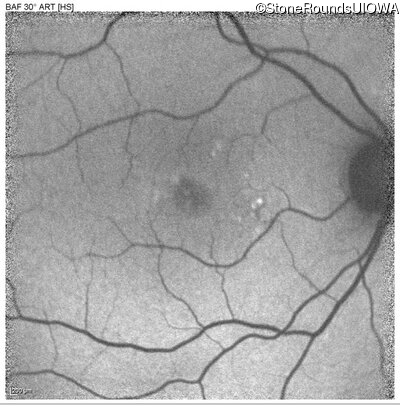

Blue Autofluorescence - Right - 20/20 -2

Exemplar